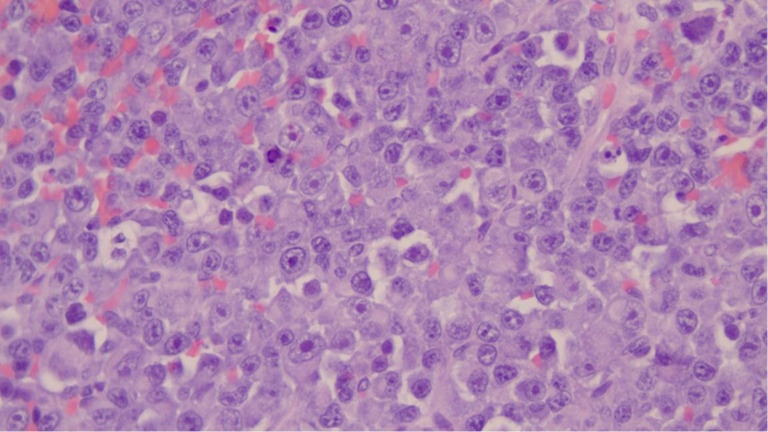

Background: Clonal hematopoiesis of indeterminate potential (CHIP) is characterized by genetic alterations associated with hematologic neoplasms, posing clinical challenges in managing concurrent hematological malignancies. CHIP may complicate the treatment landscape due to its potential to influence disease progression and treatment response. We report a 73-year-old male with multiple myeloma (MM) harboring a CHIP PPM1D mutation, elucidating the complexities and therapeutic considerations in such cases.

Case description: After four cycles of cyclophosphamide, bortezomib, and dexamethasone therapy, he achieved a partial response, followed by complete hematologic response (CR) post eight cycles of lenalidomide, dexamethasone, and bortezomib therapy. Despite this, upfront autologous hematopoietic stem cell transplantation (HSCT) was initially deemed unsuitable due to positive PPM1D CHIP status. HSCT proceeded after aggressive relapse with clonal evolution but yielded short-lived response. Following failure of >4 lines of therapy, he received chimeric antigen receptor T (CAR-T) cell therapy (ciltacabtagene autoleucel) for salvage. This approach successfully induced remission, which was maintained for 6 months.

Abstract Image